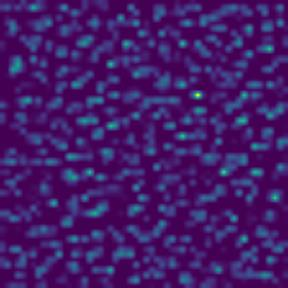

Microscopic image segmentation is a challenging task, wherein the objective is to assign semantic labels to each pixel in a given microscopic image. While convolutional neural networks (CNNs) form the foundation of many existing frameworks, they often struggle to explicitly capture long-range dependencies. Although transformers were initially devised to address this issue using self-attention, it has been proven that both local and global features are crucial for addressing diverse challenges in microscopic images, including variations in shape, size, appearance, and target region density. In this paper, we introduce SA2-Net, an attention-guided method that leverages multi-scale feature learning to effectively handle diverse structures within microscopic images. Specifically, we propose scale-aware attention (SA2) module designed to capture inherent variations in scales and shapes of microscopic regions, such as cells, for accurate segmentation. This module incorporates local attention at each level of multi-stage features, as well as global attention across multiple resolutions. Furthermore, we address the issue of blurred region boundaries (e.g., cell boundaries) by introducing a novel upsampling strategy called the Adaptive Up-Attention (AuA) module. This module enhances the discriminative ability for improved localization of microscopic regions using an explicit attention mechanism. Extensive experiments on five challenging datasets demonstrate the benefits of our SA2-Net model. Our source code is publicly available at \url{https://github.com/mustansarfiaz/SA2-Net}.